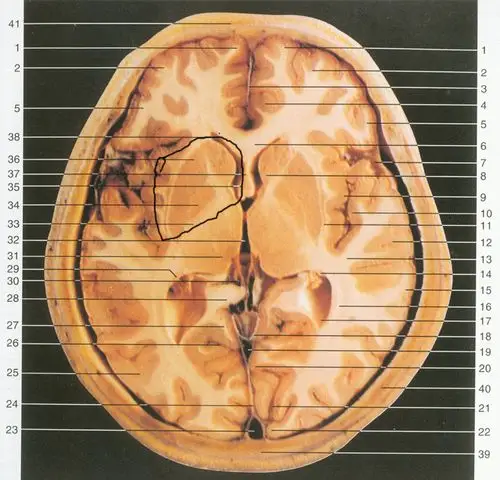

基底节区解剖位置关系图ppt模板

基底核与基底节区解剖与定位

基底节区:概念不清. 可能包括:基底节,黑质,红核,及其周围白质区域.